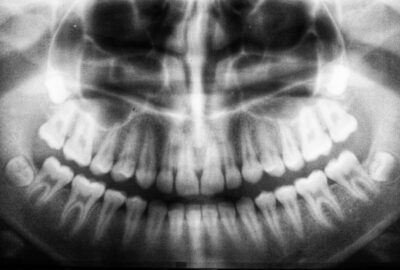

diagnostic radiologique